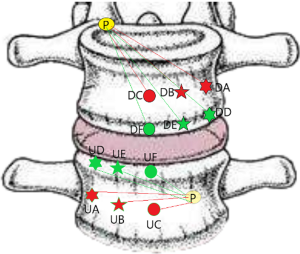

Posterior corner in lumbar spine was selected as the screw entry point (P point) for oblique fixation. The screw entry point (P point) in posterior-inferior corner is the bony area between the upper margin of the pedicle and the upper endplate. The screw entry point (P point) in posterior-superior corner is the bony area between the lower margin of the pedicle and the lower endplate (Figure 2). The corresponding targets are A, B, C, D, E, and F, respectively (A: the middle point of the contralateral anterior-middle 1/3, B: the contralateral anterior-middle point, C: the middle point of the contralateral side, D: the upper point of contralateral anterior-middle 1/3, E: the contralateral anterior-upper point, F: the middle-upper point of the contralateral side) in the contralateral anterior region (Figure 3).

In the process of oblique fixation from posterior corner in lumbar spine, each path could be divided into two groups, medium group and full-length group. The medium group included PA, PB and PC, while the full-length group included PD, PE and PF (Figure 4). The upward paths included PUA, PUB, PUC, PUD, PUE, and PUF. The downward paths included PDA, PDB, PDC, PDD, PDE, and PDF.

PUA path: distance from the posterior-lower corner of the upper vertebral body to the middle point of the contralateral anterior-middle 1/3.

PUB path: distance from the posterior-lower corner of the upper vertebral body to the contralateral anterior-middle point.

PUC path: distance from the posterior-inferior corner of the upper vertebral body to the middle point of the contralateral side.

PUD path: distance from the posterior-lower corner of the upper vertebral body to the upper point of contralateral anterior-middle 1/3.

PUE path: distance from the posterior-lower corner of the upper vertebral body to the contralateral anterior-upper point.

PUF path: distance from the posterior-lower corner of the upper vertebral body to the middle-upper point of the contralateral side.

PDA path: distance from the posterior-upper corner of the lower vertebral body to the middle point of the contralateral anterior-middle 1/3.

PDB path: distance from the posterior-upper corner of the lower vertebral body to the contralateral anterior-middle point.

PDC path: distance from the posterior-upper corner of the lower vertebral body to the middle point of the contralateral side.

PDD path: distance from the posterior-upper corner of lower vertebral body to the upper point of the contralateral anterior-middle 1/3.

PDE path: distance from the posterior-upper corner of lower vertebral body to the contralateral anterior-lower point.

PDF path: distance from posterior-upper corner of lower vertebral body to the middle-lower point of the contralateral side.